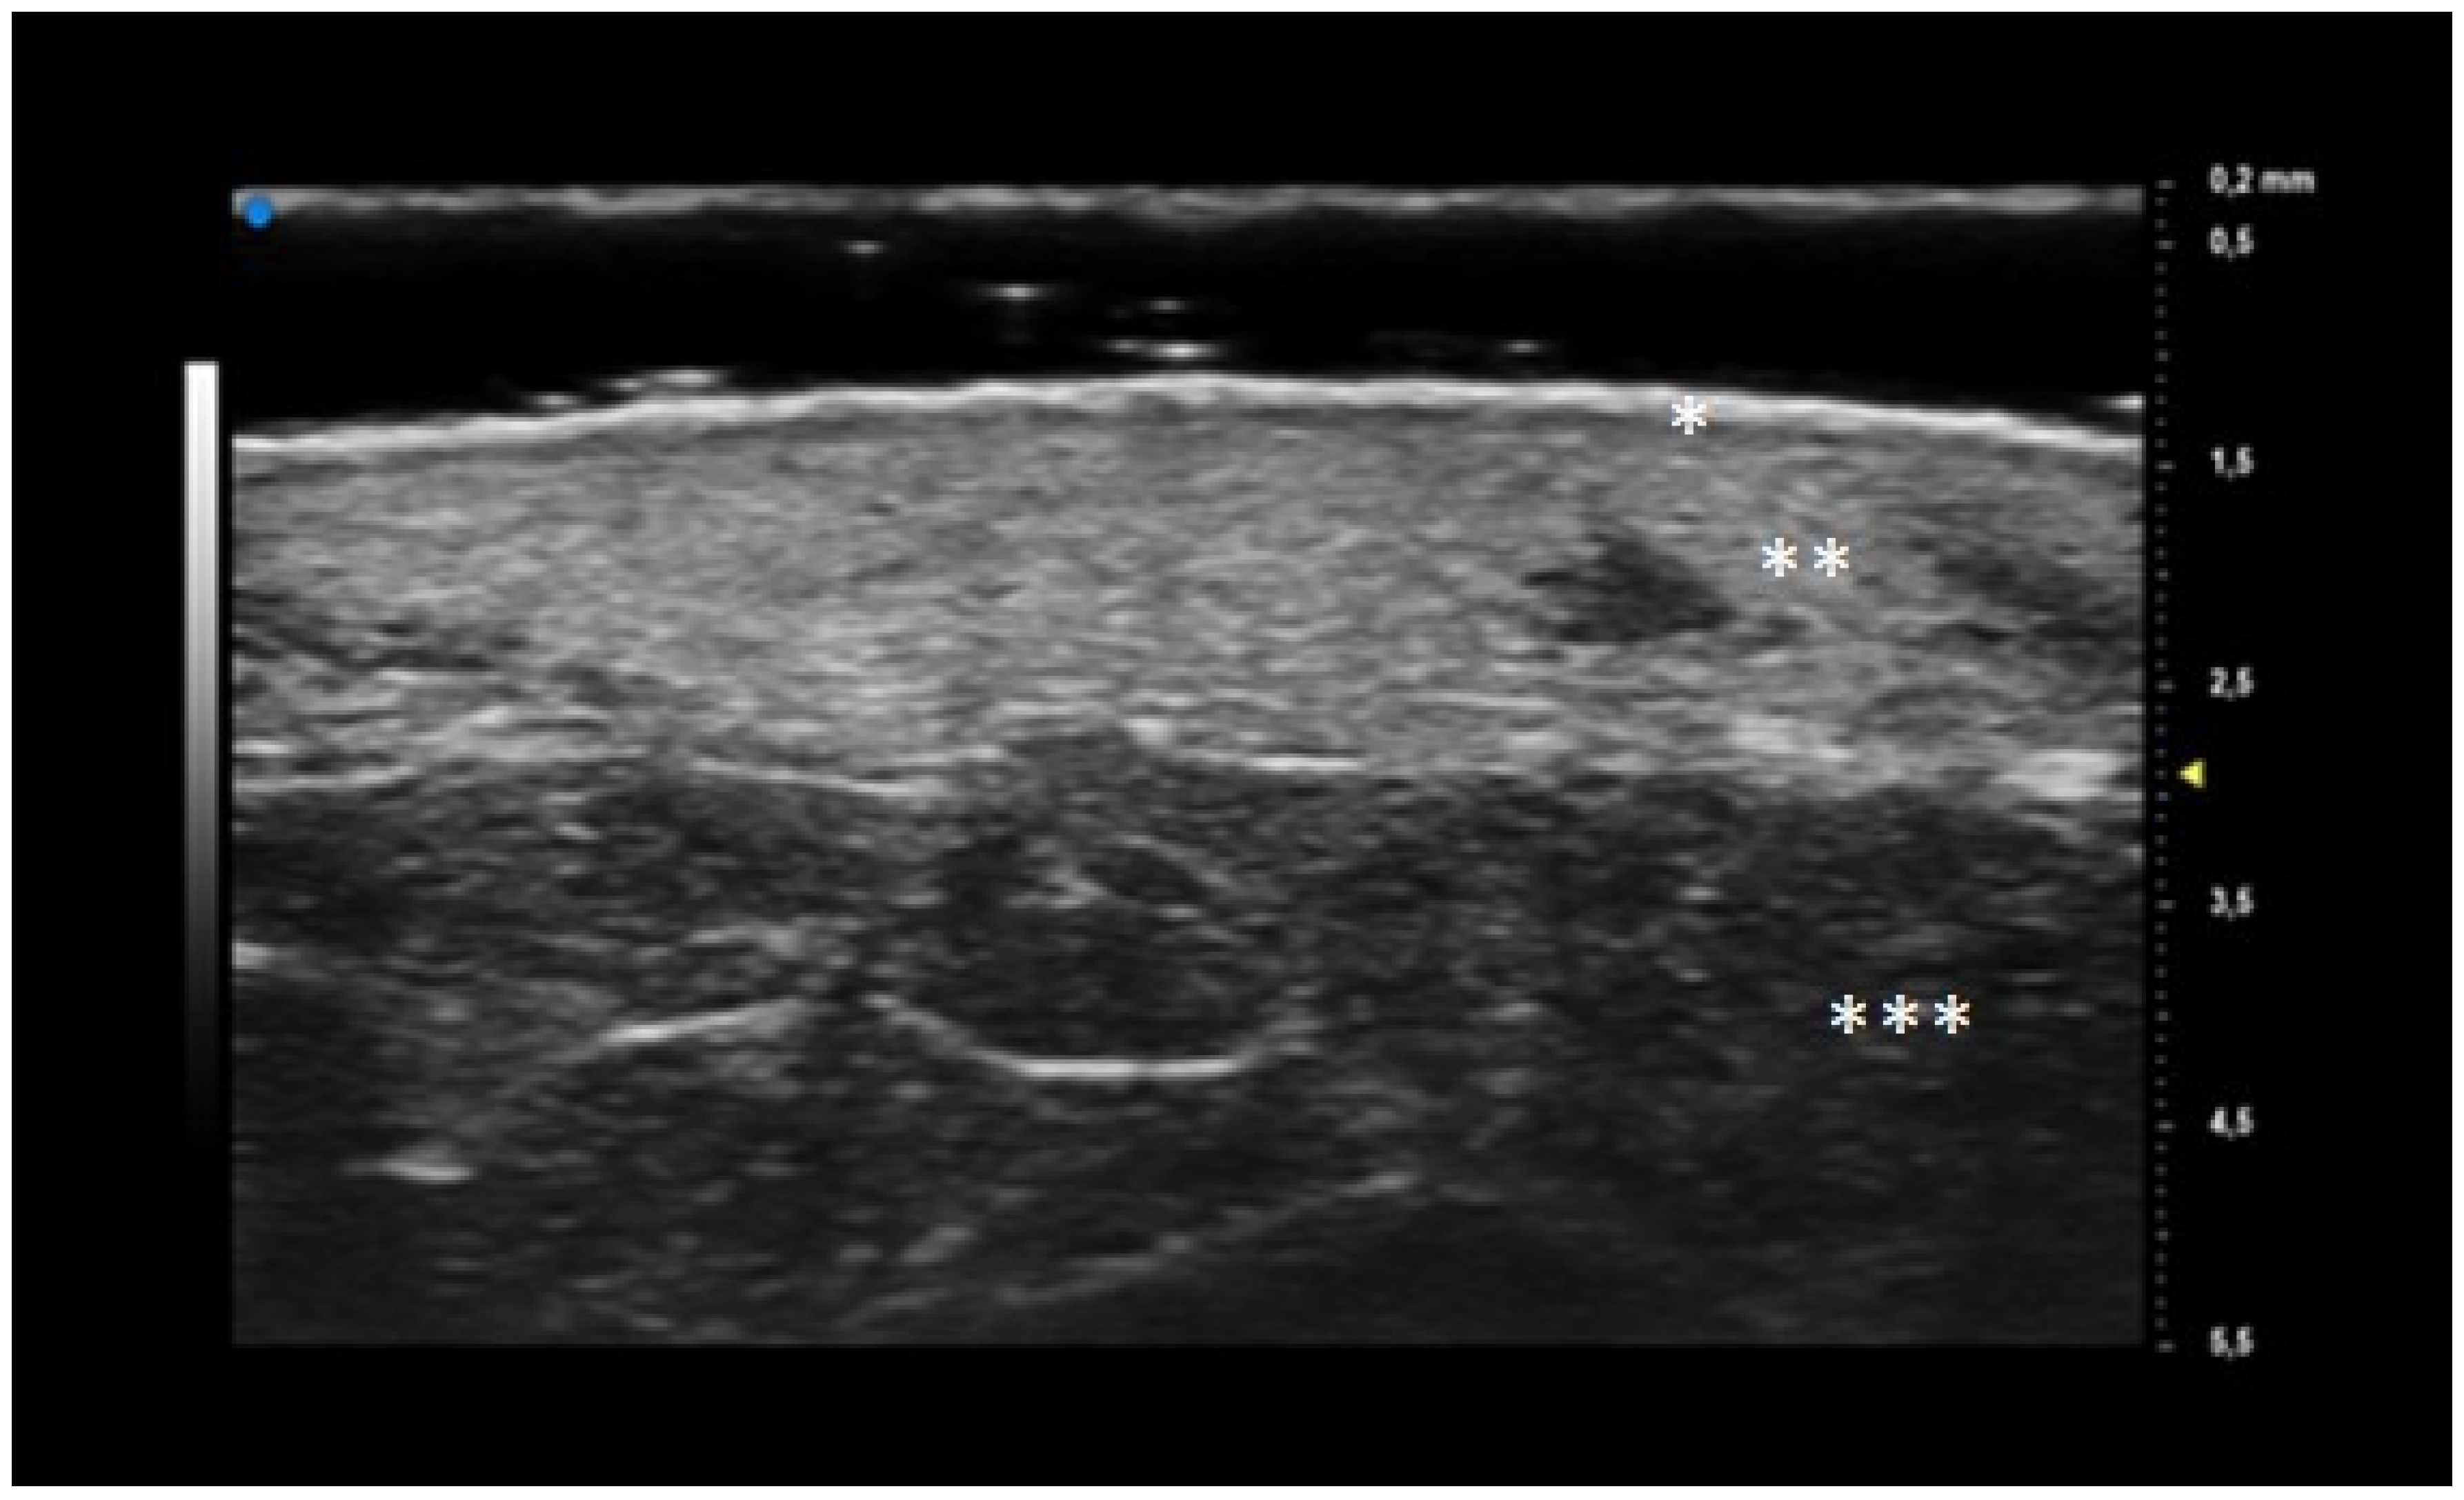

Additionally, a distinct finding emerged during the T0 UHFUS examination—an internal hyperechogenic structure within the oval entities. This internal structure, suggestive of a hair tract, was consistently identified during the initial examination (T0) but was notably absent in the follow-up examination (T1) (p value < 0.05) (Figure 3).

UHFUS examination showed the presence of a hair track within the oval hyperechoic structures in T0 and their disappearance in T1 (p-value < 0.05). This finding, as well as the increased U-shaped and V-shaped vessels in T0, could also support the idea that the pilosebaceous unit could play a pivotal role in PG pathogenesis.

The histological findings reported by Hurwitz et al. were comparable with UHFUS ones: the “hair tract” as a sign of pilosebaceous unit involvement; the “dermal hypoecogenity” as a mark of oedema; the “oval hyperechogenic structure” as neutrophilic microabscesses and the “increasing in dermal echogenicity” as increased fibroplasia in the healing phase.

Figure 1. UHFUS features of healthy skin: epidermis (*), dermis (**) and hypodermis (***).